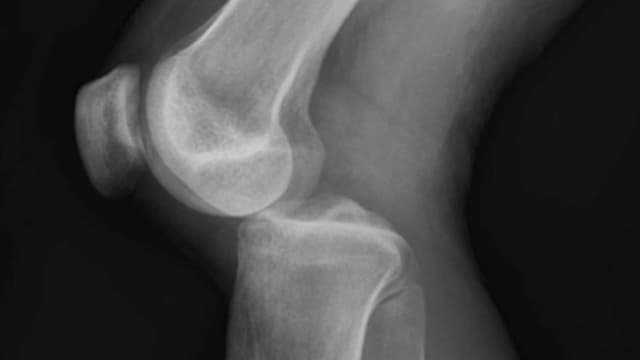

Nhận biết dấu hiệu trật khớp đầu gối và cách xử trí

Trật khớp đầu gối là một chấn thương phổ biến trong cuộc sống hàng ngày, đặc biệt ở những người thường xuyên vận động hoặc tham gia thể thao. Khi khớp đầu gối bị trật, các cấu trúc xung quanh khớp như dây chằng, cơ và mô mềm có thể bị tổn thương, gây đau […]